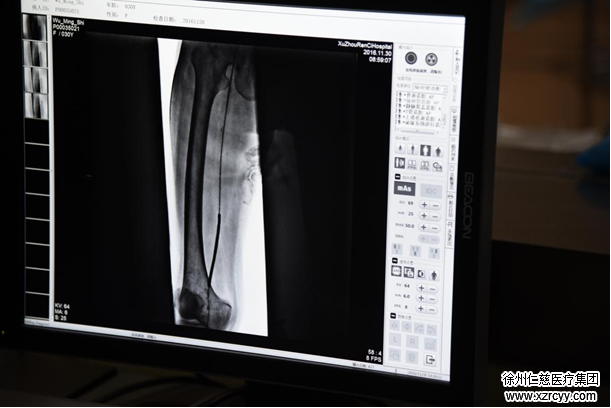

导丝疏通闭塞血管

医护人员穿上铅衣,手术正式开始。在医学影像设备的引导下,通过米粒大小的穿刺点,主刀医生将特制的导管、导丝等精密器械,引入人体,对堵塞血管进行疏通。

据了解,介入治疗是在医学影像设备的引导下,将特制的导管,导丝等精密器械,引入人体,对体内病态进行诊断和局部治疗。